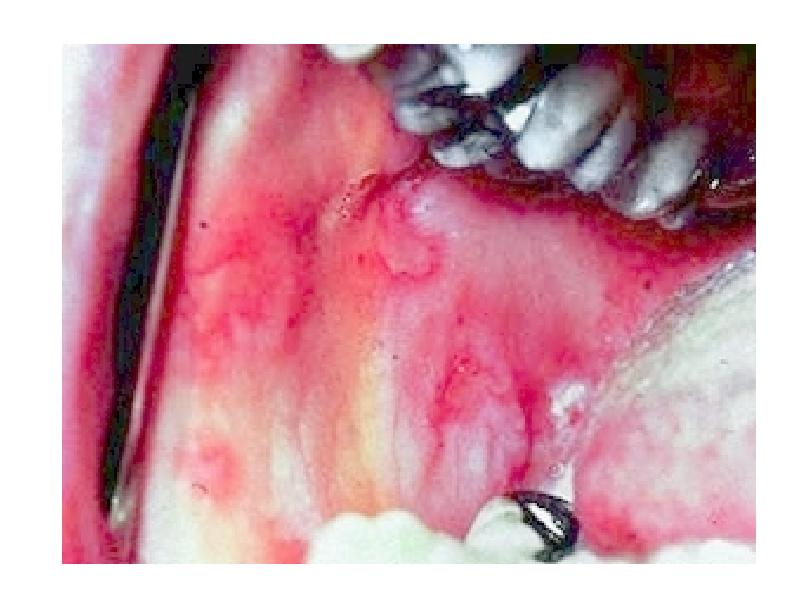

- 8. Choice of vehicles for different lesions Lesion